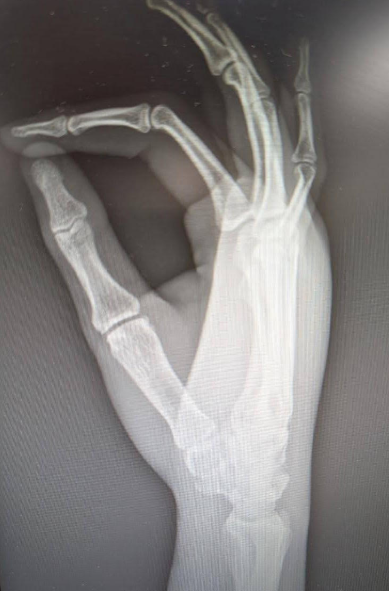

A 31-year-old male presents as a trauma after a 15 foot fall off of a ladder, landing on his outstretched right upper extremity. He has significant tenderness over his right wrist and sensation deficits of his right 3rd – 5th digits.

Show me your middle finger.. I can’t - it’s numb